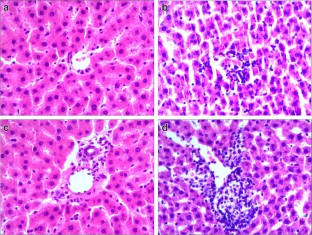

CIH treatment caused significant increase of serum alanine aminotransferase, aspartate aminotransferase, and malondialdehyde (MDA). Liver MDA was significantly higher in CIH group than that in NC group. Histology showed that CIH treatment induced discernible swelled, disordered hepatocytes, necrosis, and infiltrated inflammatory cells. CIH treatment significantly reduced the expression of GPX4, while markedly up-regulated expression of ACSL4, indicating elevation in hepatic ferroptosis. In addition, the protein expression of Nrf2 in CIH group was significantly lower than that in NC group.